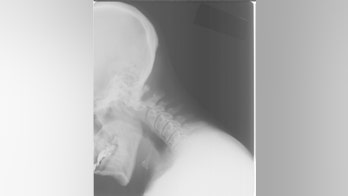

Nervous System Health - Page 134